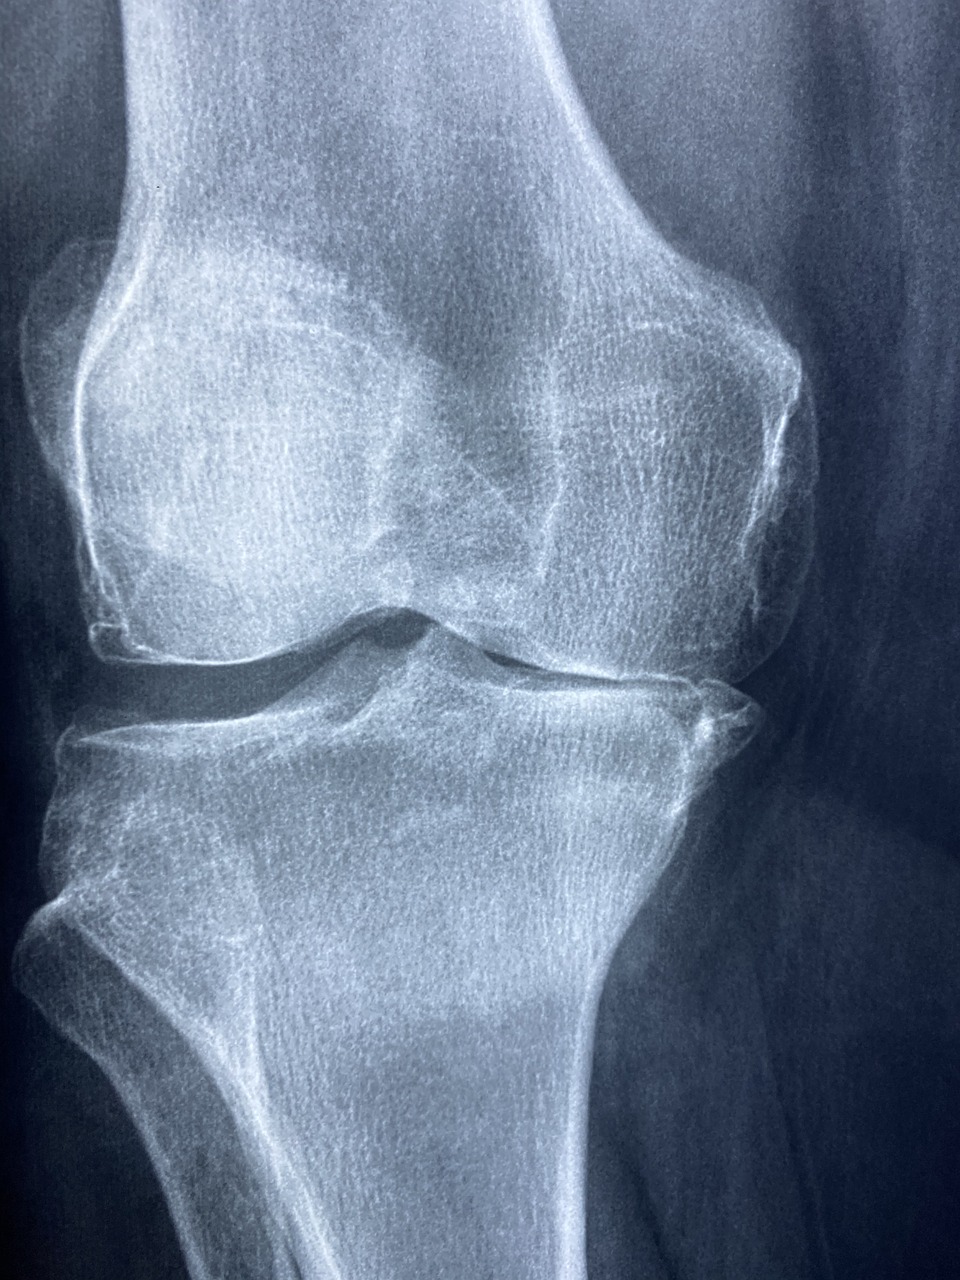

골관절염은 관절 내 뼈의 끝을 완충하는 조직인 연골이 파괴되는 퇴행성 관절 질환입니다. 시간이 지남에 따라 연골이 닳아 없어지면서 뼈가 서로 마찰을 일으켜 통증, 경직, 운동성 저하 등을 유발할 수 있습니다. 골관절염은 신체의 어떤 관절에도 영향을 미칠 수 있지만 무릎, 엉덩이, 손, 척추 등에 가장 흔하게 영향을 미칩니다. 골관절염의 위험인자로는 나이, 유전자, 비만, 관절 부상, 직업이나 스포츠 활동으로 인한 반복적인 관절 스트레스 등이 있습니다. 골관절염에 대한 치료법은 없지만, 치료는 증상을 완화하고, 관절 기능을 개선하고, 삶의 질을 향상하는 것을 목표로 합니다. 비약물학적인 개입은 골관절염 관리의 초석을 이루며 체중 감량, 운동, 물리치료 및 교정기나 부목과 같은 보조 장치를 포함할 수 있습니다. 체중 감소는 근육을 강화하고, 관절의 유연성을 개선하며, 통증을 줄이는 데 도움을 주는 반면, 체중 감소는 체중을 견디는 관절에 가해지는 하중을 줄일 수 있습니다. 골관절염 관리를 위한 약리학적 옵션에는 통증과 염증을 완화하기 위한 아세트아미노펜과 같은 처방전 없이 살 수 있는 진통제와 비스테로이드성 소염제가 포함됩니다. NSAIDs 또는 캅사이신을 포함하는 크림 또는 패치와 같은 국소 치료도 국소적인 완화를 제공할 수 있습니다. 경구 약물로 적절하게 조절되지 않는 지속적인 증상을 가진 환자에게는 코르티코스테로이드 또는 히알루론산의 관절 내 주사가 고려될 수 있습니다.